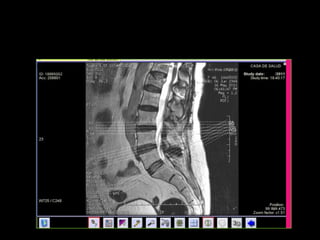

 Columna: lesiones traumáticas, lesiones del disco,…

RM: APLICACIONES  Enel campo de la ortopedia: trauma, infecciones y tumores  TRAUMATISMOS ÓSEOS, CARTÍLAGO Y PARTES BLANDAS  Edema óseo, microfracturas trabeculares, fracturas ocultas.  Lesiones ligamentarias-meniscales rodilla  Hombro: impingement, labrum, manguito, inestabilidad (ARTRO-RM)  Osteonecrosis en fase inicial (p.e.j.escafoides, astrágalo)  Columna: lesiones traumáticas, lesiones del disco,…